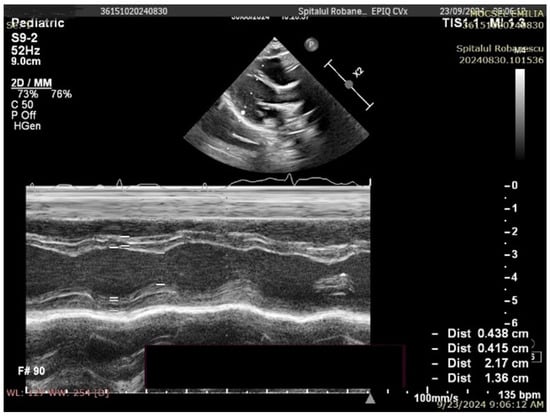

No complex congenital cardiac malformations were detected in the SMA cohort. Owing to thoracic deformities (common in the SMA), the left ventricular ejection fraction (EF) cannot be accurately measured via the Simpson method or strain rate studies; instead, fractional shortening (FS) was used to assess systolic function. All the children had normal systolic functions. Mild septal defects, such as patent foramen ovale (PFO) or small atrial septal defects (ASD), were observed. The left ventricular mass (LVM) percentile and left ventricular mass index (LVMI) significantly differed between the SMA and control groups. The median LVM percentile was 1.98% in the SMA group compared with 13.57% in the control group (p < 0.01). Similarly, the median LVMI was 50.54 in the SMA cohort and 56.27 in the control cohort (p < 0.01) (Figure 2 and Figure 3, Table 3).

Figure 3. Transthoracic echocardiography in a control group patient (8 months old, 8 kg)—M-mode measurements (LVM = 21.69 g, p = 38.97%, Z score −0.29).